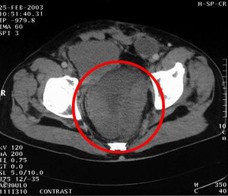

病例1 男,68歲,2006年12月14日,CT掃描發(fā)現(xiàn)胰頭占位性病變,6.0×4.7cm2,腹膜后淋巴結(jié)轉(zhuǎn)移,伴肝內(nèi)多發(fā)轉(zhuǎn)移灶。艾恒+希羅達(dá)化療3療程無效(圖1)。2007年4月5日,開始接受今又生治療,胰腺腫瘤內(nèi)注射今又生1×…今又生治療病例---胃腸腫瘤